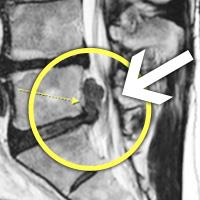

MRI ġ